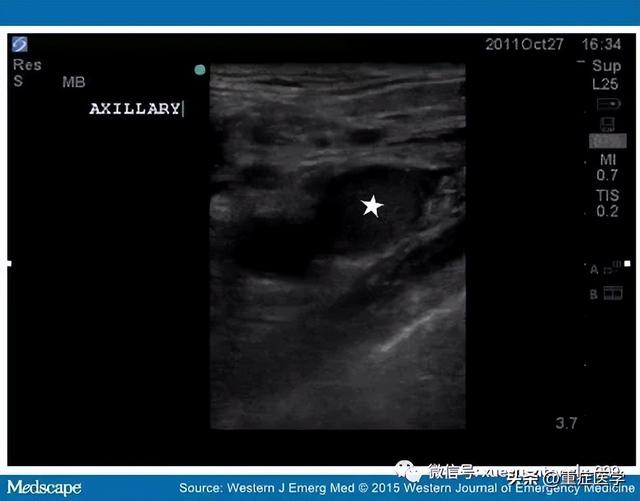

2015年Aaron Birch 博士等人发表在 Western J Emerg Med 杂志上的一篇病例报道中记录的患者就是因为静脉通路建立过程中发现的左侧无名静脉、双侧锁骨下静脉和上腔静脉内血栓。

超声显示右颈内静脉血栓(如下图)